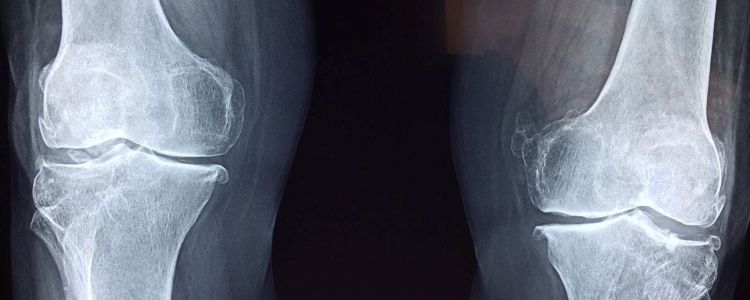

Коли кістка ламається, медичні пристрої і предмети, такі як гвинти і штифти, часто використовуються, щоб утримувати шматочки разом під час загоєння кістки. Але цей процес може бути надзвичайно болючим, довгим і важким. Одне нове технологічне диво могло б зробити ці методи застарілими. Цей потенційно змінює гру новий інструмент являє собою тривимірний друкований керамічний імплантат, який утримує зламані кістки разом, перетворюючись на справжню природну кістка.

Імплантат має подібний склад з природною кісткою, тому дослідники прийшли до висновку, що він зміг легко розчинятися без будь-яких токсичних побічних ефектів і об'єднатися в кістки, тому що «тіло не може відрізнити», - сказав Зрейкат. Імплантат пористий і діє як ешафот, який може рости природними кістками і кровоносними судинами, що робить його, мабуть, ідеальним інструментом у відновленні кістки.

Зокрема, імплантат складається з силікату кальцію, мінерального гахніта і невеликих кількостей стронцію і цинку, які є мікроелементами в природної кістки.